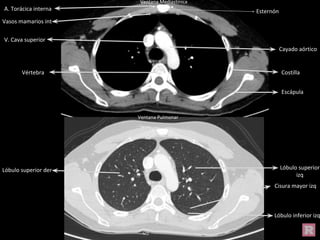

Cayado aórtico

V. Cava superior

Costilla

Escápula

Esternón

Vértebra

A. Torácica interna

Vasos mamarios int

Lóbulo inferior izq

Lóbulo superior der Lóbulo superior

izq

Cisura mayor izq